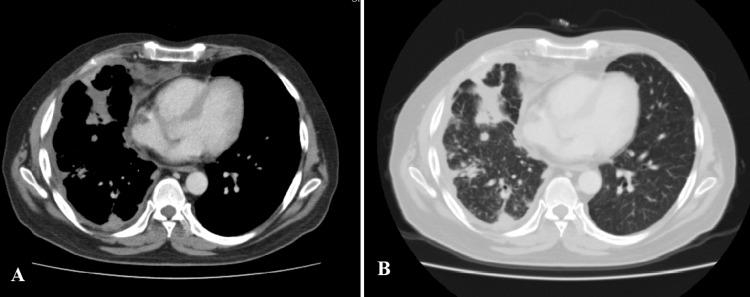

Nocardia is a rare gram-positive pathogen reported to cause infections in immunocompromised individuals. It usually involves the lungs but may also lead to abscess formation; cases of disseminated nocardiosis have also been reported. We are presenting a case of an Asian male who had sarcoidosis with pulmonary and skin involvement. The patient was on long-term immunosuppressive therapy with corticosteroids with good control of the disease. He developed a fever, weight loss, and right-sided chest pain. CT of the chest showed new nodular infiltrates. Worsening of sarcoidosis was suspected; the corticosteroid dose was increased and methotrexate was started. There was no favorable response to the increase in immunosuppressive therapy. Weight loss was followed by worsening shortness of breath and fluctuant swelling in the right lateral half of the chest. Bronchoalveolar lavage was done to rule out tuberculosis but it did not show any organism's growth. Ultrasound-guided needle aspiration from the abscess was done that showed growth of Nocardia species. Therapeutic dose co-trimoxazole (trimethoprim-sulphamethoxazole) was started as first-line therapy after confirming the organism's drug susceptibility pattern along with needle aspiration of the collection on the chest wall. Immunosuppressive agents were stopped. There was a good response to treatment with resolution of symptoms within two months. However, complete radiological recovery took 10 months. Co-trimoxazole (trimethoprim-sulphamethoxazole) therapy continued for two months after radiological recovery. Physicians, therefore, should keep Nocardia as an important differential diagnosis while treating the immunosuppressed population.

诺卡菌是一种罕见的革兰氏阳性病原体,据报道可在免疫功能低下的个体中引起感染。它通常累及肺部,但也可能导致脓肿形成;也有播散性诺卡菌病的病例报道。我们报告一例患有结节病且累及肺部和皮肤的亚洲男性病例。该患者长期接受糖皮质激素免疫抑制治疗,疾病控制良好。他出现发热、体重减轻和右侧胸痛。胸部CT显示有新的结节状浸润影。怀疑结节病病情恶化;增加了糖皮质激素剂量并开始使用甲氨蝶呤。免疫抑制治疗增加后未见好转。体重减轻后,呼吸急促加重,右侧胸部外侧出现波动性肿胀。进行支气管肺泡灌洗以排除结核病,但未发现任何微生物生长。对脓肿进行超声引导下针吸活检,结果显示诺卡菌生长。在确定微生物的药敏模式后,开始使用治疗剂量的复方新诺明(甲氧苄啶-磺胺甲恶唑)作为一线治疗,并对胸壁的积液进行针吸。停用免疫抑制剂。治疗反应良好,症状在两个月内缓解。然而,影像学完全恢复需要10个月。影像学恢复后,复方新诺明(甲氧苄啶-磺胺甲恶唑)治疗持续了两个月。因此,医生在治疗免疫抑制人群时应将诺卡菌作为重要的鉴别诊断。